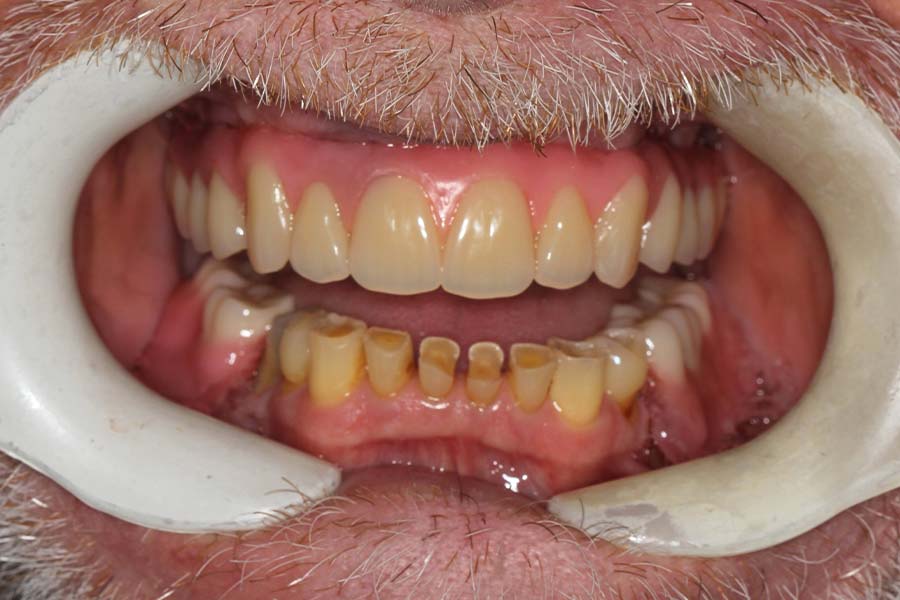

After many years of postponing, the time had come for this patient to fix his teeth. He elected to start on the upper and move to the lower one year later.

Frontal view of upper implant bridge (intra-oral). Just because the patient is delaying treatment on the lower doesn’t mean we can’t improve it for the year he is waiting. See next picture.

The lower teeth were bonded with composite resin to improve aesthetics and function during the year he is waiting to do his lower.

Smile of upper permanent and lower bonded teeth. The patient is starting to learn how to smile, again!